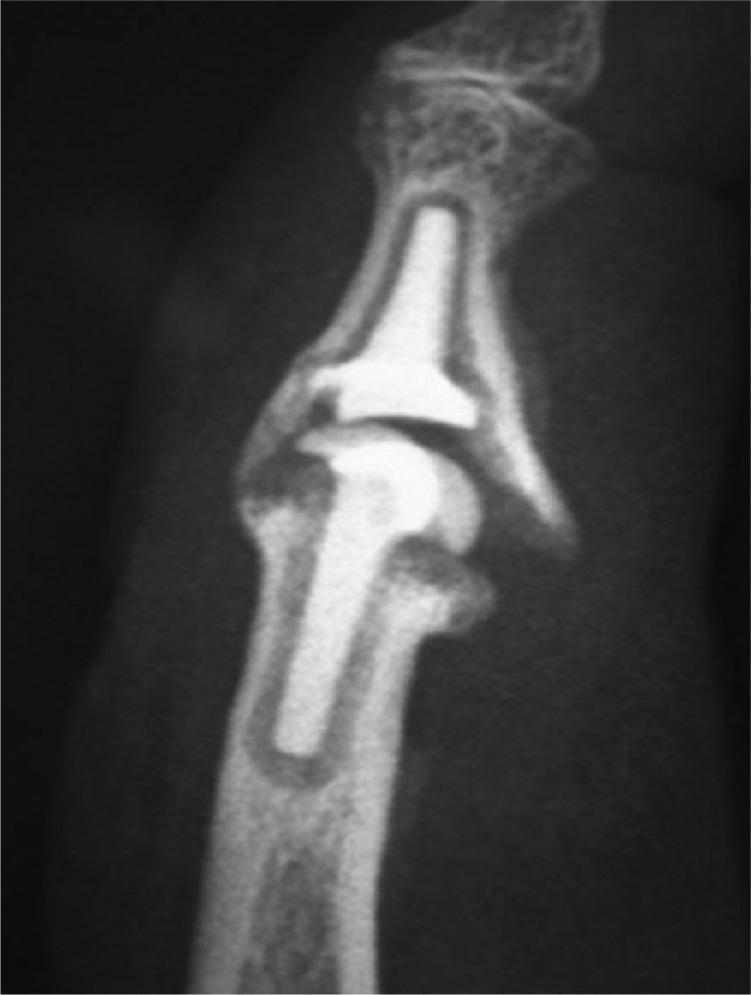

Until the late 1980s, proximal interphalangeal (PIP) joint reconstruction had been almost exclusively performed by the use of monobloc silicone spacers and associated with acceptable to good clinical outcomes.More recently, new materials such as metal-on-polyethylene and pyrocarbon implants were proposed, associated with good short-term and mid-term results.Pyrocarbon is a biologically inert and biocompatible material with a low tendency to wear. PIP pyrolytic implants are characterised by a graphite core, visible on radiographs and covered by a radiolucent outer layer of pyrocarbon.New surgical techniques and better patient selection with tailored rehabilitative protocols, associated with the knowledge arising from the long-term experience with pyrocarbon implants, has demonstrated noteworthy clinical outcomes over the years, as demonstrated by recent studies. Cite this article: 2017;2:21-27. DOI: 10.1302/2058-5241.2.160041.

直到20世纪80年代末,近端指间(PIP)关节重建几乎一直仅通过使用整块硅胶间隔物来进行,并且临床结果可接受或良好。最近,提出了诸如金属对聚乙烯和热解碳植入物等新材料,其短期和中期结果良好。热解碳是一种生物惰性和生物相容性材料,磨损倾向低。PIP热解植入物的特征是有一个石墨芯,在X线片上可见,被一层不透射线的热解碳外层覆盖。新的手术技术、更好的患者选择以及量身定制的康复方案,再加上热解碳植入物长期经验所积累的知识,多年来已显示出显著的临床结果,近期研究已证明这一点。引用本文:2017;2:21 - 27。DOI:10.1302/2058 - 5241.2.160041。